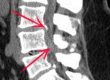

As radiografias simples são suficientes para a documentação da espondilolistese. Em alguns casos são necessários exames mais detalhados como cintilografia óssea, tomografia e ressonância magnética.

Cada caso tem uma indicação específica de realizar ou não exames de imagem.